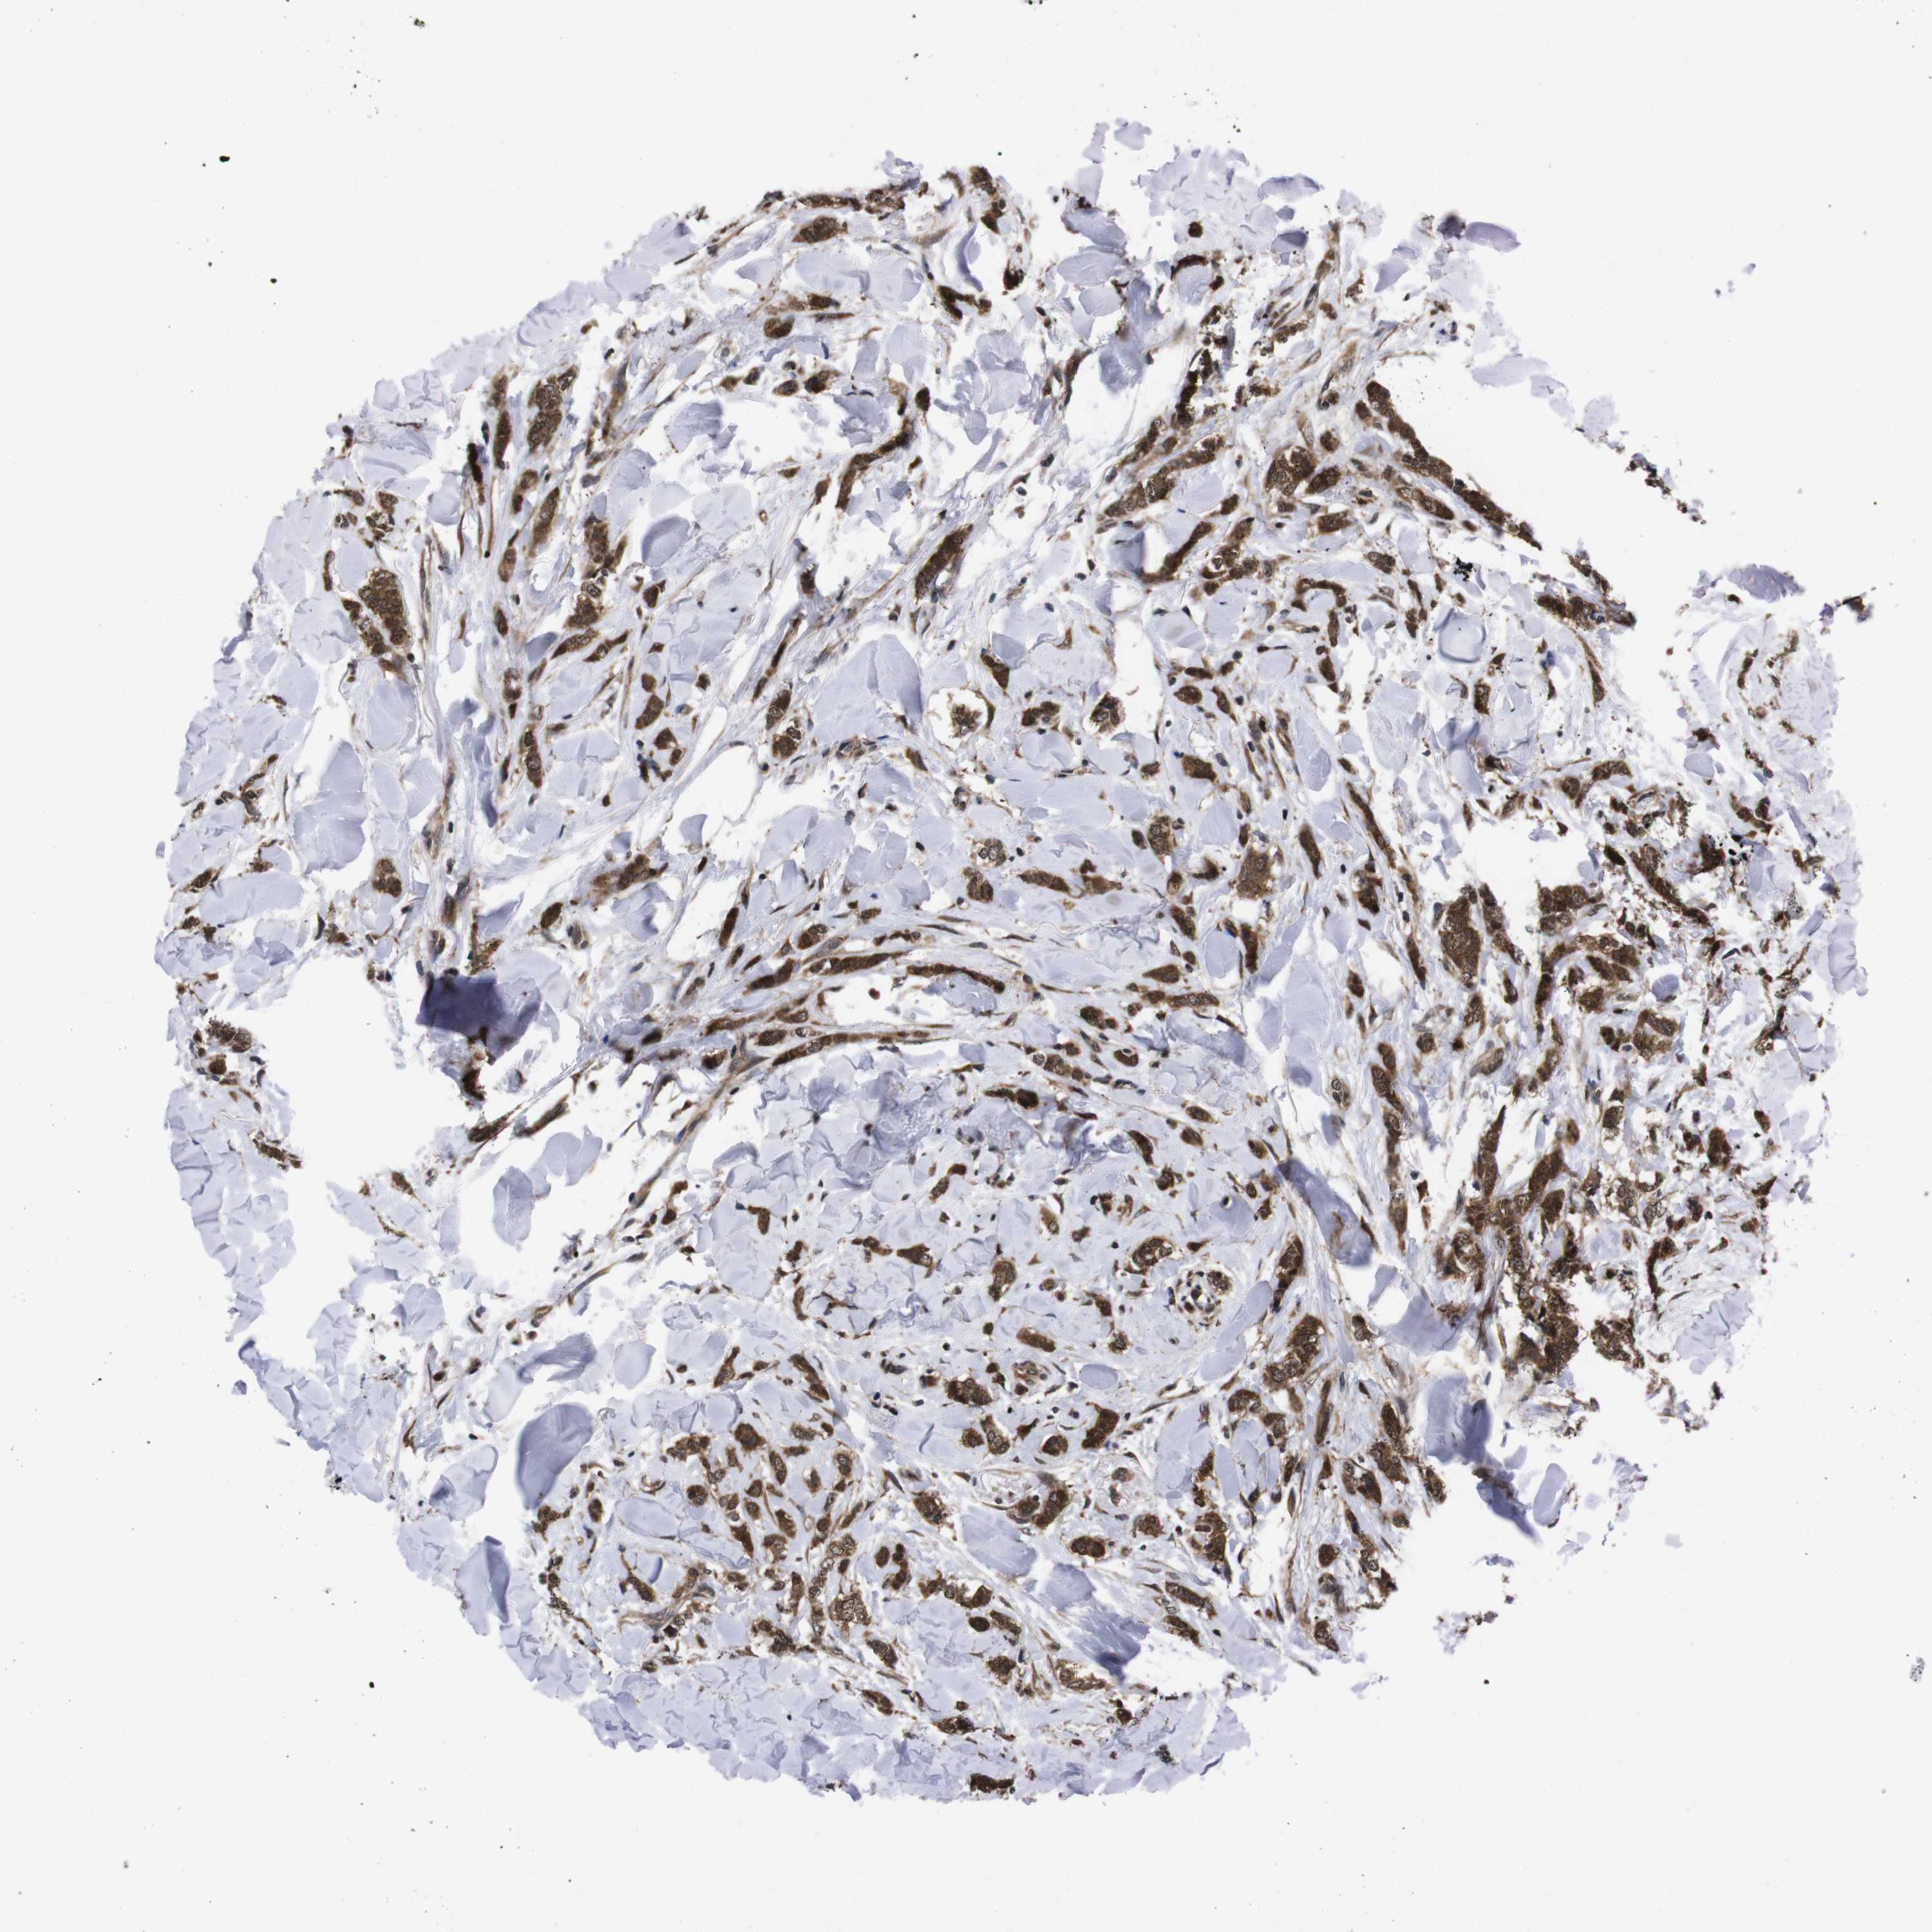

BRCA TCGA BRCA VALIDATION PROTEIN EXPRESSION